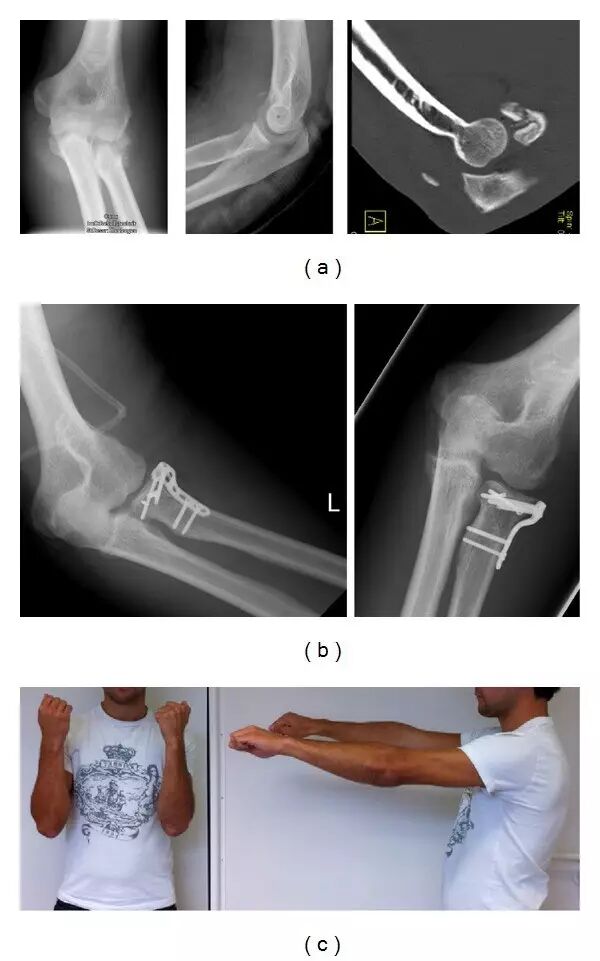

(a)示出桡骨头部多碎片断裂的X射线。 CT扫描的一个切片证明一个年轻的运动学生患有肘关节脱臼的三头肌的骨腱撕裂。 (b)术后X射线显示桡骨头重建和稳定。 将三头肌腱的骨撕裂缝合到鹰嘴尖。 (c)创伤后48周,年轻运动员不能伸直左肘。 通过应用口服可的松治疗,使用如表2所述的降低剂量的泼尼松龙5m剂,在6周内恢复全范围的运动。